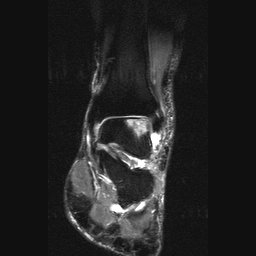

Return to Osteochondritis Dissecans